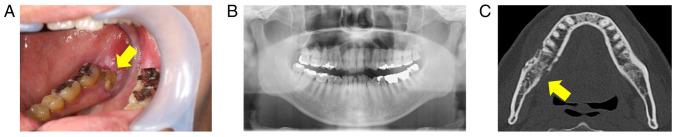

Osteoradionecrosis (ORN) of the jaw is a severe complication of radiotherapy for head and neck cancer. Extensive surgical resection has shown promising outcomes; however, patients' prognosis must be considered. Papillary thyroid carcinoma (PTC) generally has a favorable prognosis, whereas metastatic PTC is considered a refractory disease against conventional treatment. Recently, comprehensive genomic profiling (CGP) has enabled clinicians to provide personalized medicine, offering patients with intractable disease further therapeutic options. The present case study reported on a patient with advanced PTC who developed ORN during lenvatinib treatment; extensive surgical treatment with submandibular dissection for ORN provided a favorable outcome. Pathological examination unexpectedly revealed PTC metastases in the dissected right submandibular gland. Postoperatively, the patient experienced worsening metastases to the lung and liver. CGP identified a CCDC6-RET fusion, prompting selpercatinib treatment, which achieved a partial response. This report aims to emphasize that extensive surgical treatment for ORN should be considered, even in patients with advanced cancer, if the patients' condition is stable. In addition, submandibular dissection is warranted in selected patients, particularly when thyroid cancer exhibits an aggressive phenotype with occult metastases. Furthermore, this report highlights the importance of integrating personalized medicine in the management of advanced cancer cases and emphasizes the availability of genomic profiling to guide treatment decisions.

颌骨放射性骨坏死(ORN)是头颈部癌放疗的一种严重并发症。广泛的手术切除已显示出有前景的结果;然而,必须考虑患者的预后。甲状腺乳头状癌(PTC)通常预后良好,而转移性PTC被认为是一种对传统治疗难治的疾病。最近,全面基因组分析(CGP)使临床医生能够提供个性化医疗,为患有难治性疾病的患者提供更多治疗选择。本病例研究报告了一名晚期PTC患者,在乐伐替尼治疗期间发生ORN;针对ORN进行的包括下颌下淋巴结清扫的广泛手术治疗取得了良好结果。病理检查意外发现右侧下颌下腺切除标本中有PTC转移灶。术后,患者出现肺和肝转移恶化。CGP检测到CCDC6-RET融合,促使使用塞尔帕替尼治疗,获得了部分缓解。本报告旨在强调,即使是晚期癌症患者,如果病情稳定,也应考虑对ORN进行广泛手术治疗。此外,对于选定的患者,特别是当甲状腺癌表现出具有隐匿性转移的侵袭性表型时,有必要进行下颌下淋巴结清扫。此外,本报告强调了在晚期癌症病例管理中整合个性化医疗的重要性,并强调了基因组分析对指导治疗决策的可用性。